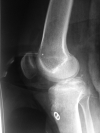

Objective: to assess twenty two cases of isolated PCL avulsion fractures from tibial insertion, arthroscopically treated with suture pull technique, and to evaluate achieved clinical outcomes in terms of radiographic laxometry (objective) and Lysholm scale (subjective).

Material and method: Study includes 22 cases operated between April 2014 and March 2017. Patients less than 18 years old, presentation after 3 weeks of injury, concomitant injury in the same limb, with open wounds or with comminuted avulsed fragment were excluded from the study. All cases were MRI proven. All arthroscopic suture fixation technique was used in all cases. Follow up was done at 3 weeks, 6 weeks, 3 months, 6 months and 12 months. Mean follow up was one year. Subjective complaints, Knee flexion, Lysholm score and stress radiographs were noted.

Results: Average Lysholm score was 96.3. Seventeen patients had excellent results and Five had good results based on Lysholm scores. In two patients, grade 2 laxity (5-10 mm) was present on stress radiographs but there were no clinical complaints. All patients achieved osseous union and had no functional limitation. Three Patients developed arthrofibrosis initially but gained functional range later.